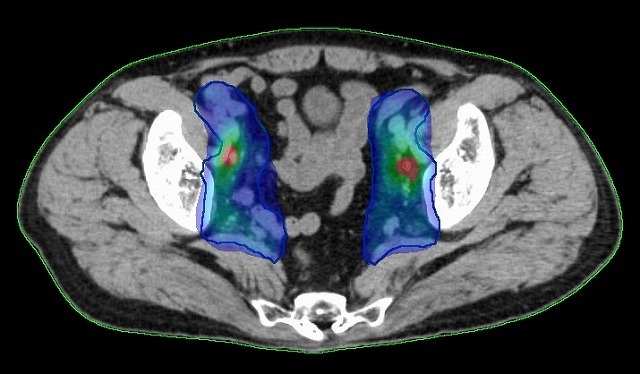

IMRTを用いて肛門がんと転移しやすいリンパ節領域に照射。